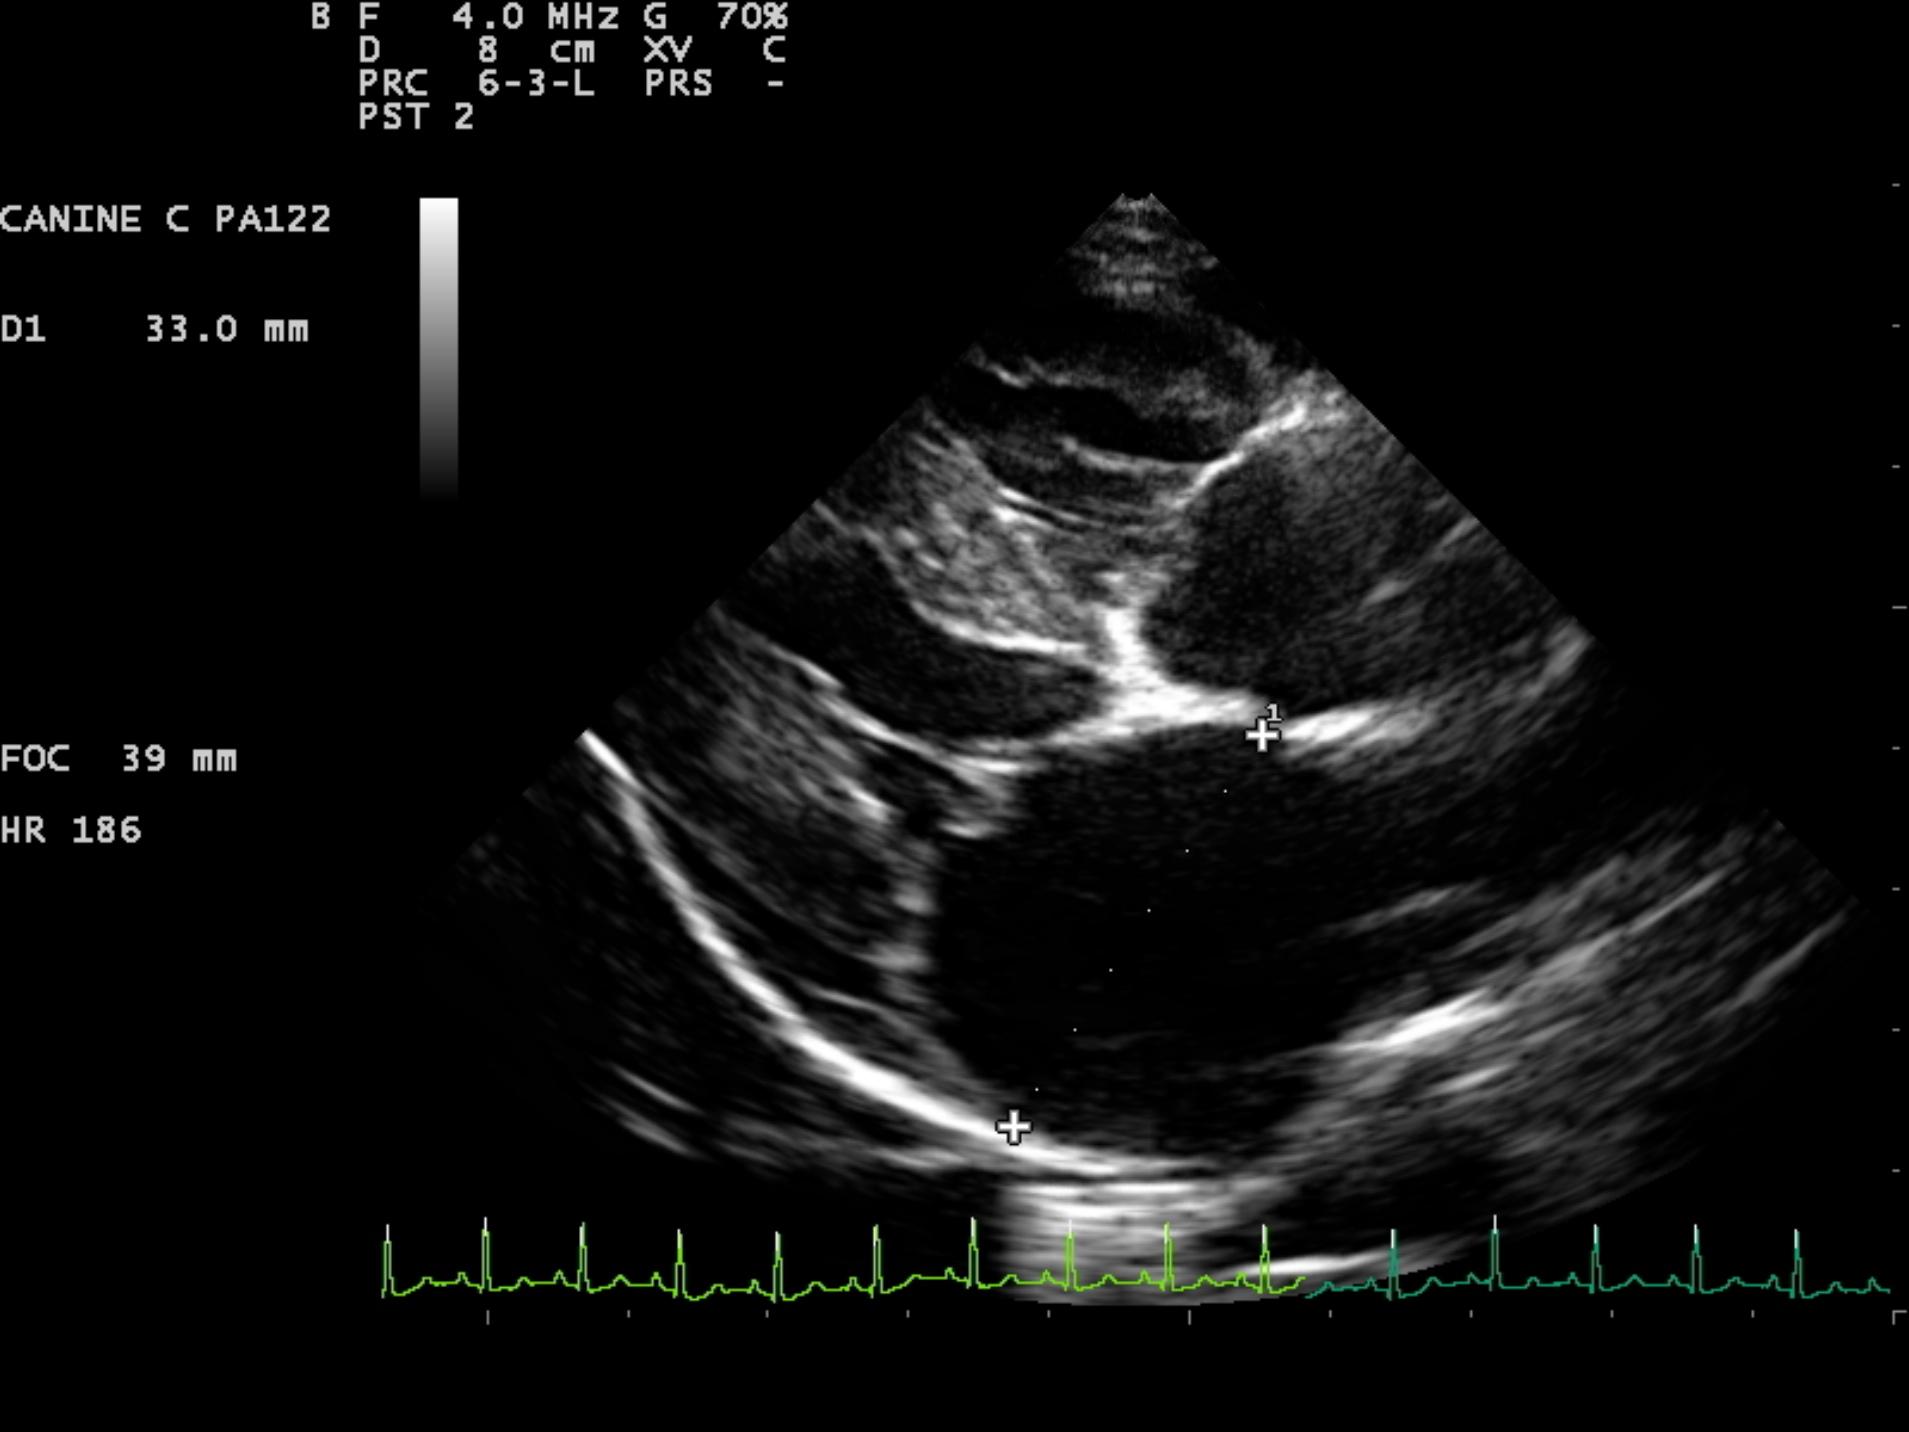

An 8-year-old F Maltese was presented for examination. A grade 5/6 systolic heart murmur was noted. Radiographs revealed severe generalized cardiomegaly and an unremarkable pulmonary parenchyma. Moderate hepatomegaly and ascites was additionally noted.